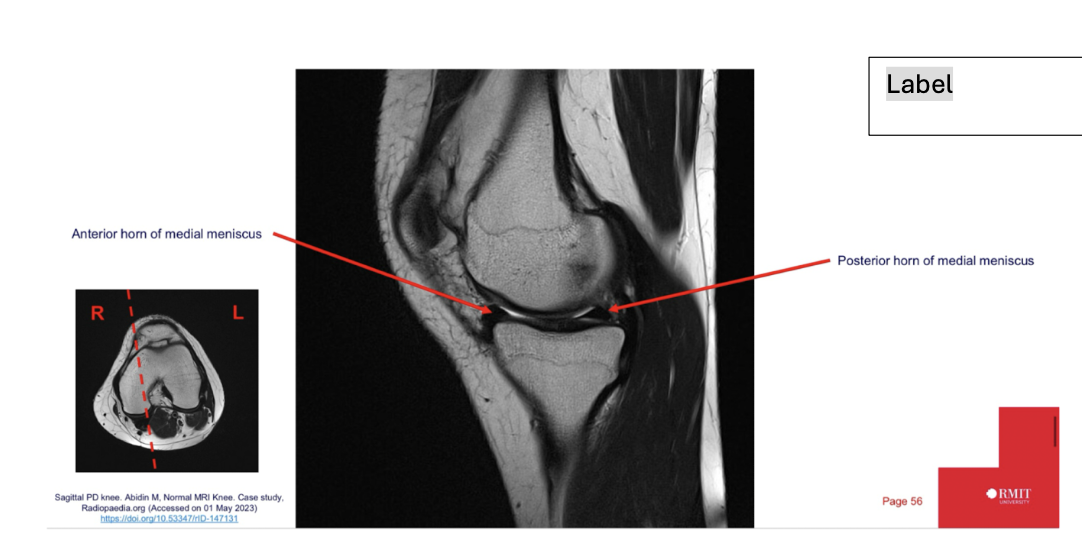

Sequence + pathology?

• 1st = PD: intermediate signal from muscle and fat is bright, image quality is much better

• 2nd = PD FS: fat has been supressed appearing much darker

• Path = complete ACL tear: in a normal knee you would see a black band which is the acl sitting

across the anterior aspect of the tibia and extending to the posterior aspect on the femur. This is not present at all hence, a tear.